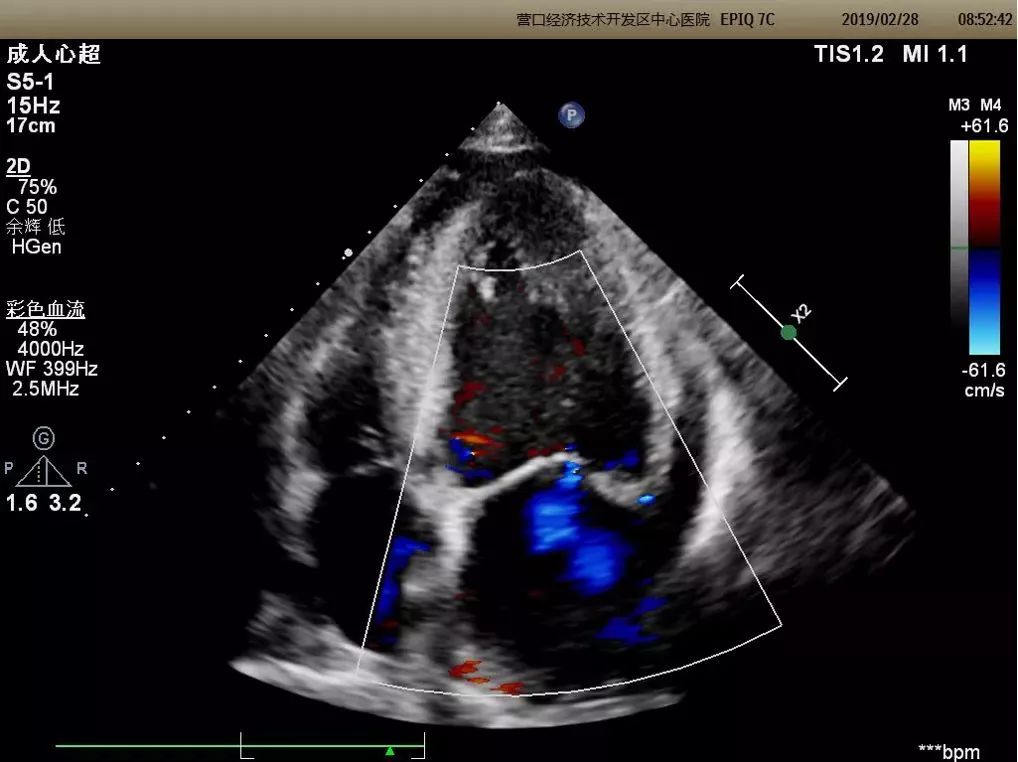

心脏三维超声成像

能够整体、直观的获得心脏内部结构图像,医生可多角度、多切面观察,适用于瓣膜病、先天性心脏病等疾病,使超声诊断更加准确。

二维成像